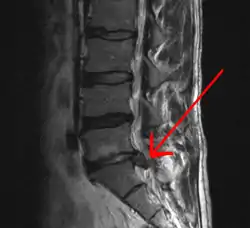

MRI scan of large herniation (on the right) of the disc between L4 and L5 vertebrae

A rather severe herniation of the L4–L5 disc

- Magnetic resonance imaging is the gold standard study for confirming a suspected LDH. With a diagnostic accuracy of 97%, it is the most sensitive study to visualize a herniated disc due to its significant ability in soft tissue visualization. MRI also has higher inter-observer reliability than other imaging modalities. It suggests disc herniation when it shows an increased T2-weighted signal at the posterior 10% of the disc. Degenerative disc diseases have shown a correlation with Modic type 1 changes. When evaluating for postoperative lumbar radiculopathies, the recommendation is that the MRI is performed with contrast unless otherwise contraindicated. MRI is more effective than CT in distinguishing inflammatory, malignant, or inflammatory etiologies of LDH. It is indicated relatively early in the course of evaluation (<8 weeks) when the patient presents with relative indications like significant pain, neurological motor deficits, and cauda equina syndrome. Diffusion tensor imaging is a type of MRI sequence used for detecting microstructural changes in the nerve root. It may be beneficial in understanding the changes that occur after herniated lumbar disc compresses a nerve root, and might help in differentiating the patients that need surgical intervention. In patients with a high suspicion of radiculopathy due to lumbar disc herniation, yet the MRI is equivocal or negative, nerve conduction studies are indicated.[43] T2-weighted images allow for clear visualization of protruded disc material in the spinal canal.